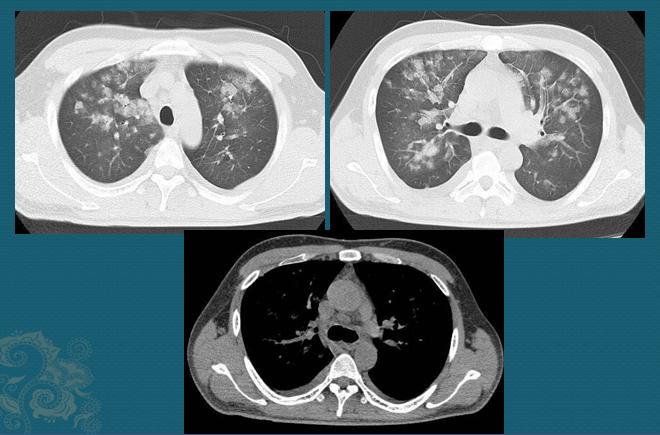

最近十几天开始尿血,最近8天开始咳嗽,并且痰中带血,每天大约出现10ml,于是安排了胸部CT:

1.上面两张白色的图片是肺窗,可以看到双肺多发的白色小斑片影,部分呈磨玻璃影,沿着小树枝状的肺血管周围分布,大部分边界不清晰,部分有融合;

2.下面的灰*图色**像是纵隔窗,用来观察纵隔软组织结构的,可见纵隔内数个稍大淋巴结,还有双侧少量胸腔积液(胸腔背侧弧形条带状影)。